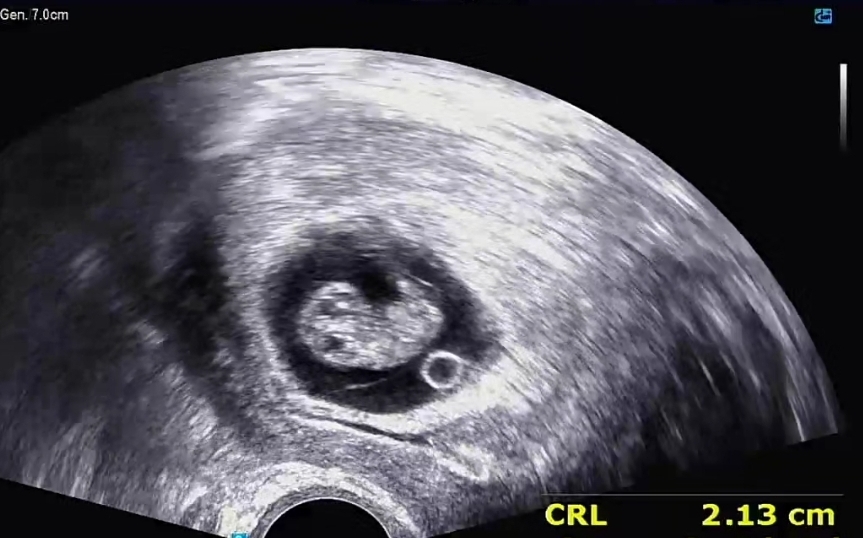

9주차 드디어 사람모양ㅋㅋ

2주전엔 무슨 0.98센티 무슨 길쭉하게 생긴게 애기라고 그래서 1센티도 안되는게 심장이 어디에 달려있는것을까.. 했는데 ㅋㅋㅋㅋㅋㅋ 2주만에 나름 아가 모양인거같아서 넘 귀여워요ㅠㅠ 난황 달랑달랑 달고 있는것도 넘 귀엽구!! 3주 뒤에 오라는데 그땐 진짜 더더 사람모양(?)이겠죠? 엄청 기다려져요 🧐💕 뱃속에서 심장 하나가 더 뛰고 있다는게 아직도 안 믿겨지네용 배크기에 비해 아가집이 좀 좁은 것 같기도하고ㅋㅋㅋㅋㅋㅋ

질초음파요! 같은 주수에 저보다 더 큰 아가들도 많은거같아서 아가마다 다 다른거같아요 ㅎㅎ 넘 걱정하지 마세용 잘 크고 있을겁니다❣️